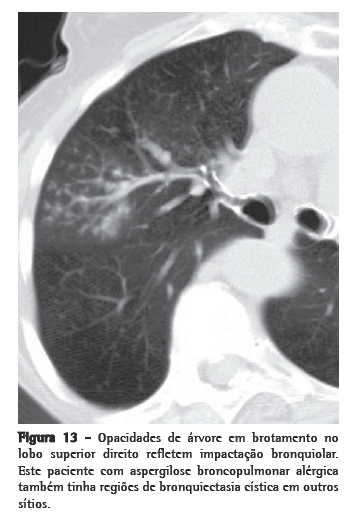

Nódulos centrolobulares

A parte central do lóbulo pulmonar secundário contém os ramos dos bronquíolos terminais, suas respectivas artérias pulmonares e, adjacente a estas, o tecido conjuntivo de suporte com vasos linfáticos. Portanto, opacidades nodulares centrolobulares podem ser o produto de doenças bronquiolares e peribronquiolares assim como de doenças vasculares e perivasculares. Atenuação em mosaico associada a aprisionamento aéreo na TCAR expiratória, ou evidências funcionais de obstrução de fluxo aéreo indica doenças envolvendo as vias aéreas periféricas. Nódulos centrolobulares algumas vezes são acompanhados pelas chamadas opacidades de "árvore em brotamento", nas quais a anormalidade lembra uma árvore brotando (Figura 13). Na maioria dos casos, o padrão de árvore em brotamento ocorre como resultado de doenças infecciosas. Árvore em brotamento é um subtipo do padrão centrolobular. Patologicamente, esta anormalidade representa impactação bronquiolar e é quase sempre devida a infecções. O Quadro 7

detalha o diagnóstico diferencial.